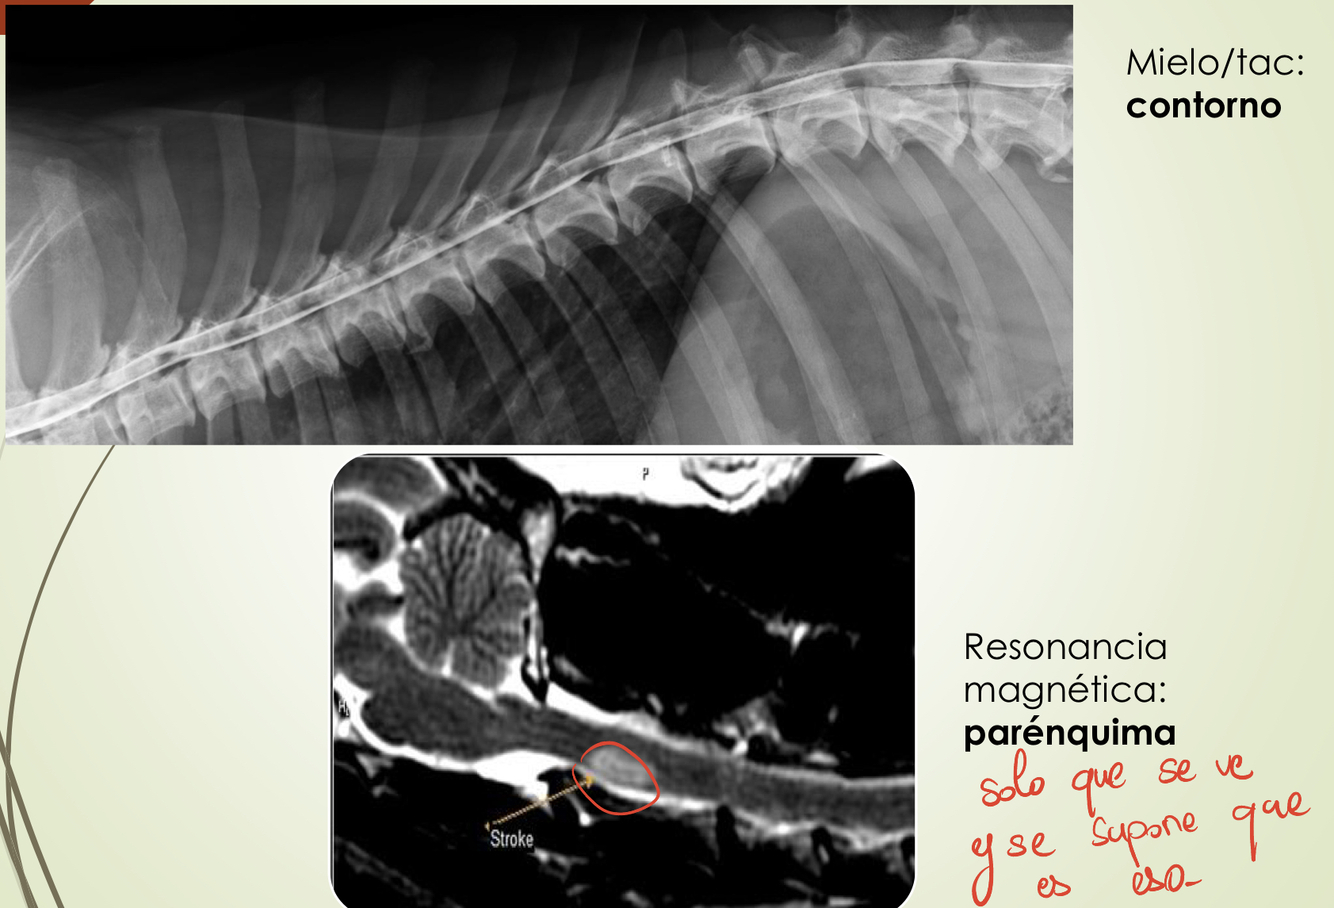

Sospecha clinica

Hansen I y II → diagnostico por imagen

* Rs : insuficiente para confirma hernia

* Mielografia

* TAC

* RM

Si no hay compresión :

* Meningitis

* Hernia aguda no compresiva

* tromboembolismo